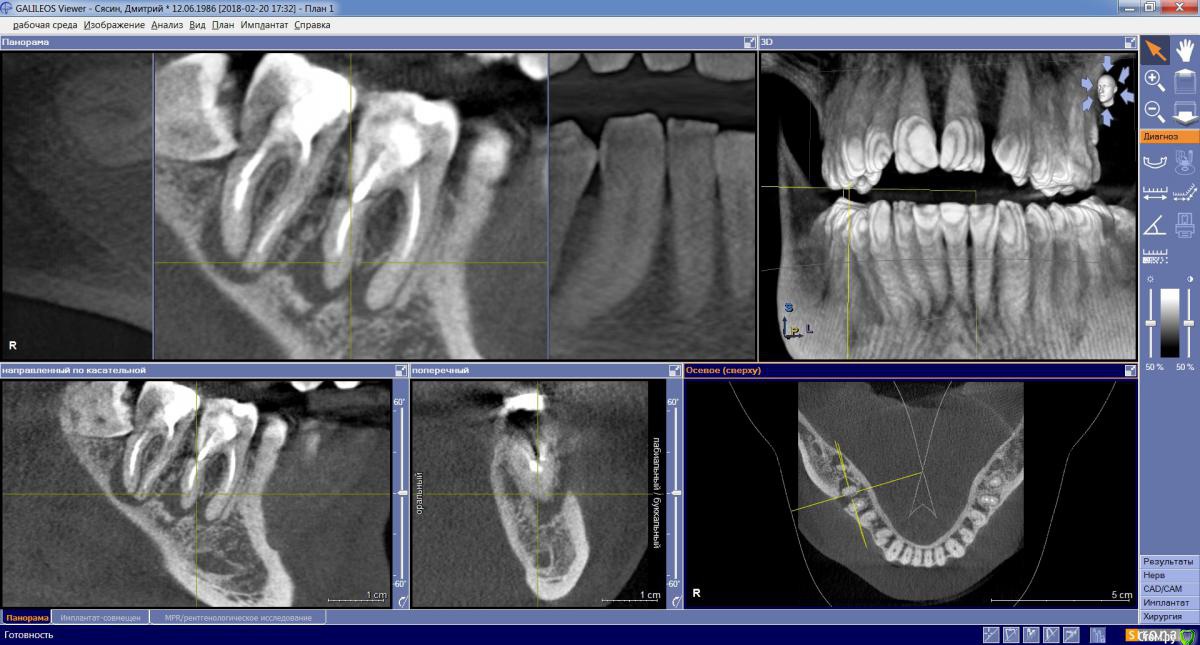

dims5 Опубликовано 21 февраля, 2018 Поделиться Опубликовано 21 февраля, 2018 Добрый день!Подскажите пожалуйста,если какая-либо надежда сохранить зубы 6-7? Зубы были пролечены несколько лет назад, не беспокоили длительное время и вот сейчас вылез свищ.Очень хочется сохранить зубы, а врач настаивает на удалении и постановке имплантов. Хотелось бы если есть хоть какая-то надежда попробовать из вылечить.Скриншоты сделал в разных нескольких разрезах чтобы лучше было видно состояние.Спасибо! Ссылка на комментарий

DmitrySH Опубликовано 21 февраля, 2018 Поделиться Опубликовано 21 февраля, 2018 Если судить только по снимку, то вполне нормальные шансы на сохранение зубов 6 и 7.А вот 8 надо убирать Ссылка на комментарий

dims5 Опубликовано 21 февраля, 2018 Автор Поделиться Опубликовано 21 февраля, 2018 Если судить только по снимку, то вполне нормальные шансы на сохранение зубов 6 и 7.А вот 8 надо убирать Большое спасибо за мнение! А вы посмотрели на второй снимок(файл 1.jpg) на нем как раз видны размеры кист( воспаления) ? Ссылка на комментарий

DmitrySH Опубликовано 21 февраля, 2018 Поделиться Опубликовано 21 февраля, 2018 А вы посмотрели на второй снимок(файл 1.jpg) на нем как раз видны размеры кист( воспаления) ? Конечно, это не сильно принципиально Ссылка на комментарий